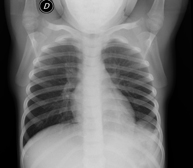

- Chest X-ray

This technique uses X-ray rendered imaging for examining the thoracic cavity (heart, lungs, costal arches, clavicles, etc.).

A chest X-ray uses a small dose of radiation to obtain a two-dimensional image of the thoracic cavity and its contents (lungs, heart, mediastinum, etc.). It is one of the most commonly performed medical tests.